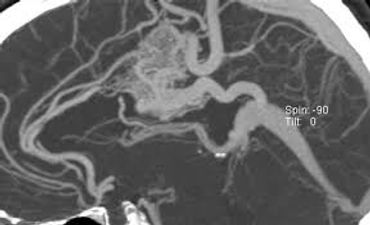

A brain arteriovenous malformation (AVM) is an abnormal tangle of blood vessels connecting arteries and veins in the brain. This tangle disrupts the normal flow of blood and can cause various health issues, including bleeding in the brain (hemorrhage).

Diagnosing a brain AVM involves several steps: